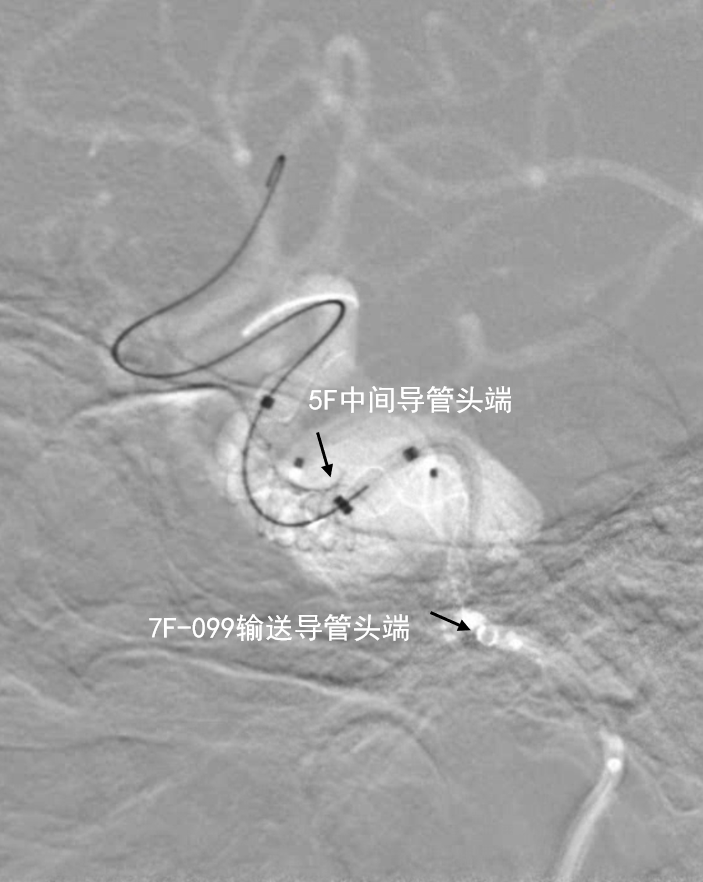

- 全麻,右侧股动脉穿刺,深瑞达7F 80cm输送导管内衬5F造影导管超选入颈内动脉C2段。5F中间导管到位至C6段,支架微导管到位至大脑中动脉M1段,弹簧圈微导管到位至动脉瘤腔内。释放第一枚5.0*45mm血流导向密网支架,支架覆盖瘤颈,近端部分陷入瘤体。

第一枚支架完全释放,深瑞达7F输送导管提供近端支撑

5F中间导管输送至第一枚血流导向密网支架内提高支撑力

- 第一枚血流导向密网支架释放后造影

深瑞达7F输送导管正位造影

深瑞达7F输送导管侧位造影